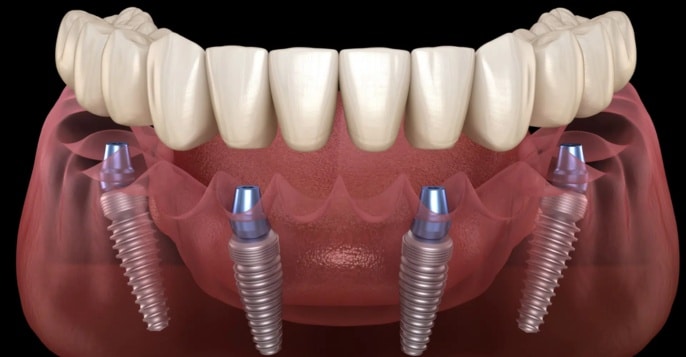

Introduction Rehabilitation of missing teeth has come a long way from removable or semi-fixed complete dentures to fixed rehabilitation using […]